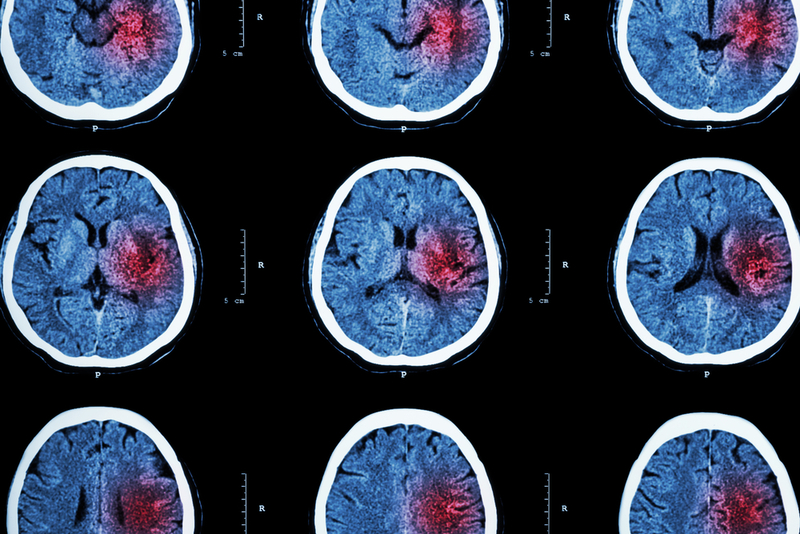

People who suffer a stroke caused by bleeding in the brain—known as brain hemorrhage—can take common medicines without raising their risk of another stroke, a major clinical trial has found.

The team found that people who took antiplatelet medicines experienced fewer recurrences of brain hemorrhage compared with those who did not take these treatments. Some 12 people suffered a brain bleed while taking the medication compared with 23 people who did not take medication.

This may suggest the treatments reduce rather than increase risk of further bleeding in the brain, the researchers say, but further studies are needed to confirm this. Around half of the participants underwent an additional brain scan using magnetic resonance imaging (MRI) at the beginning of the study. These scans are often used by doctors to check for the presence of tiny blood deposits in the brain, known as microbleeds, which can be a warning sign of future strokes.